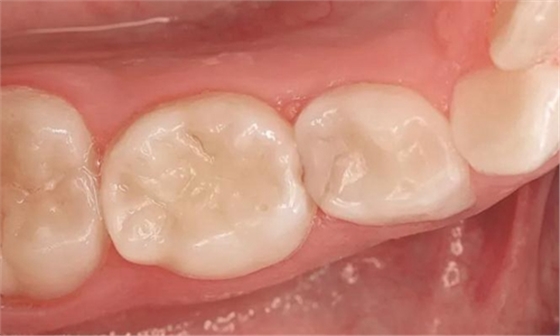

圖8:84號乳牙II類洞復(fù)合體充填2年后